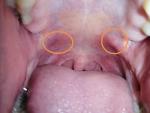

Здравствуйте, заболело горло начало отдавать в уши, поставили хронический тонзилит, фарингит, лечилась 2 месяца полосканием, антибиотики, спреями, ничего не помогает, сейчас промывают миндалины от гноя. На небной дужке все это время появилось красное пятно, бугорочек, болит. Так же на язычке неровности. Что это может быть? Очень переживаю

Пила антибионити флемоксин салютаб, пшикала люголем, гексаспреем, рассасывала таблетки имудон, фарингосепс, лизобакт, полоскала ромашкой солью содой. Миндалины промываю у врача на аппарате тонзилор. + сейчас появились 2 бугра, приносят дискомфорт, боль, фото прикладываю